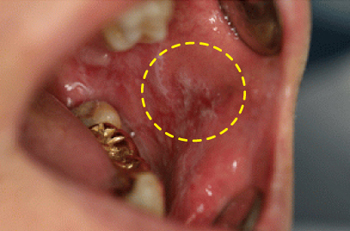

이 부위는 처음에는 구강 점막이 헐고 잘 낫지 않는 경우가 대부분으로 간단한 염증이라고 생각하고 지내기가 쉬운데, 염증이 잘 낫지 않고 2~3주 이상 같은 부위에 지속적으로 있다가 어느 순간부터는 조그만 궤양이 커지거나 단단한 혹이 생겨나게 됩니다.

[혀의 아랫면에 발생한 편평상피세포암]